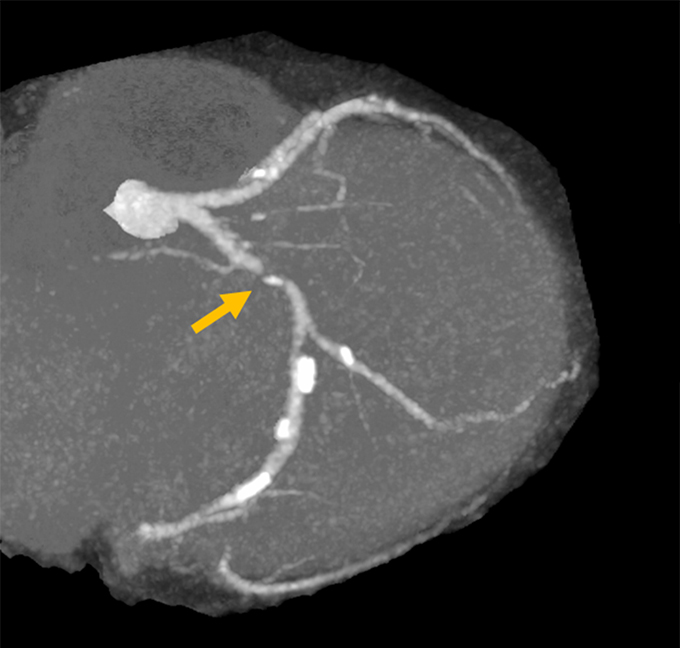

- junkankinaika-img05a-20200229